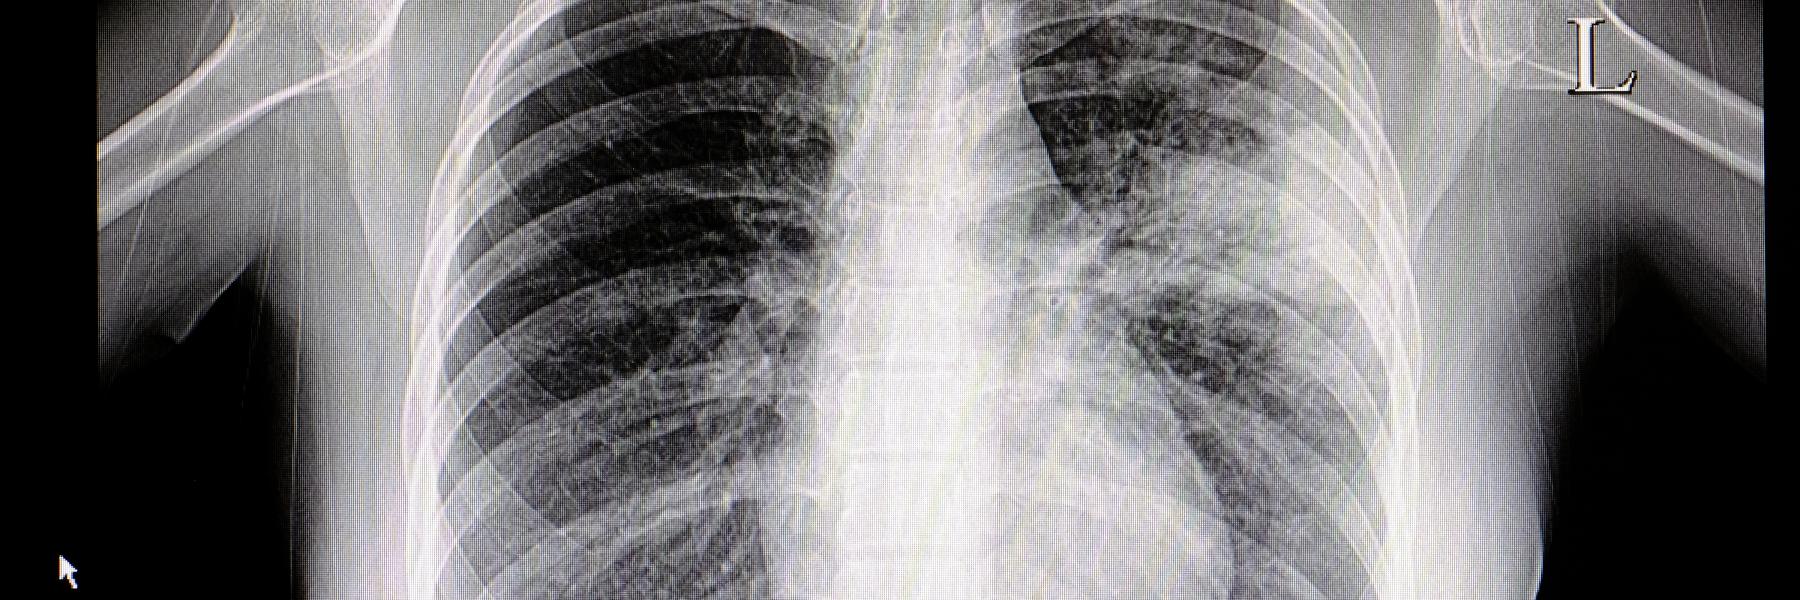

تليف الرئة من الأمراض الخطيرة التي قد تصيب الإنسان لما له من مضاعفات خطيرة، ويحدث نتيجة هذا المرض نقص فى كمية الأكسجين المتجهة إلى كافة أجهزة الجسم مما يسبب العديد من المضاعفات الخطيرة، مثل اضطراب فى ضربات القلب.

ولا ينتقل مرض التليف الرئوي بالوراثة، إلا أن الأبحاث أثبتت أن 10-15% من مرض التليف الرئوي يوجد لهم فرد آخر من العائلة مصاب بنفس المرض.